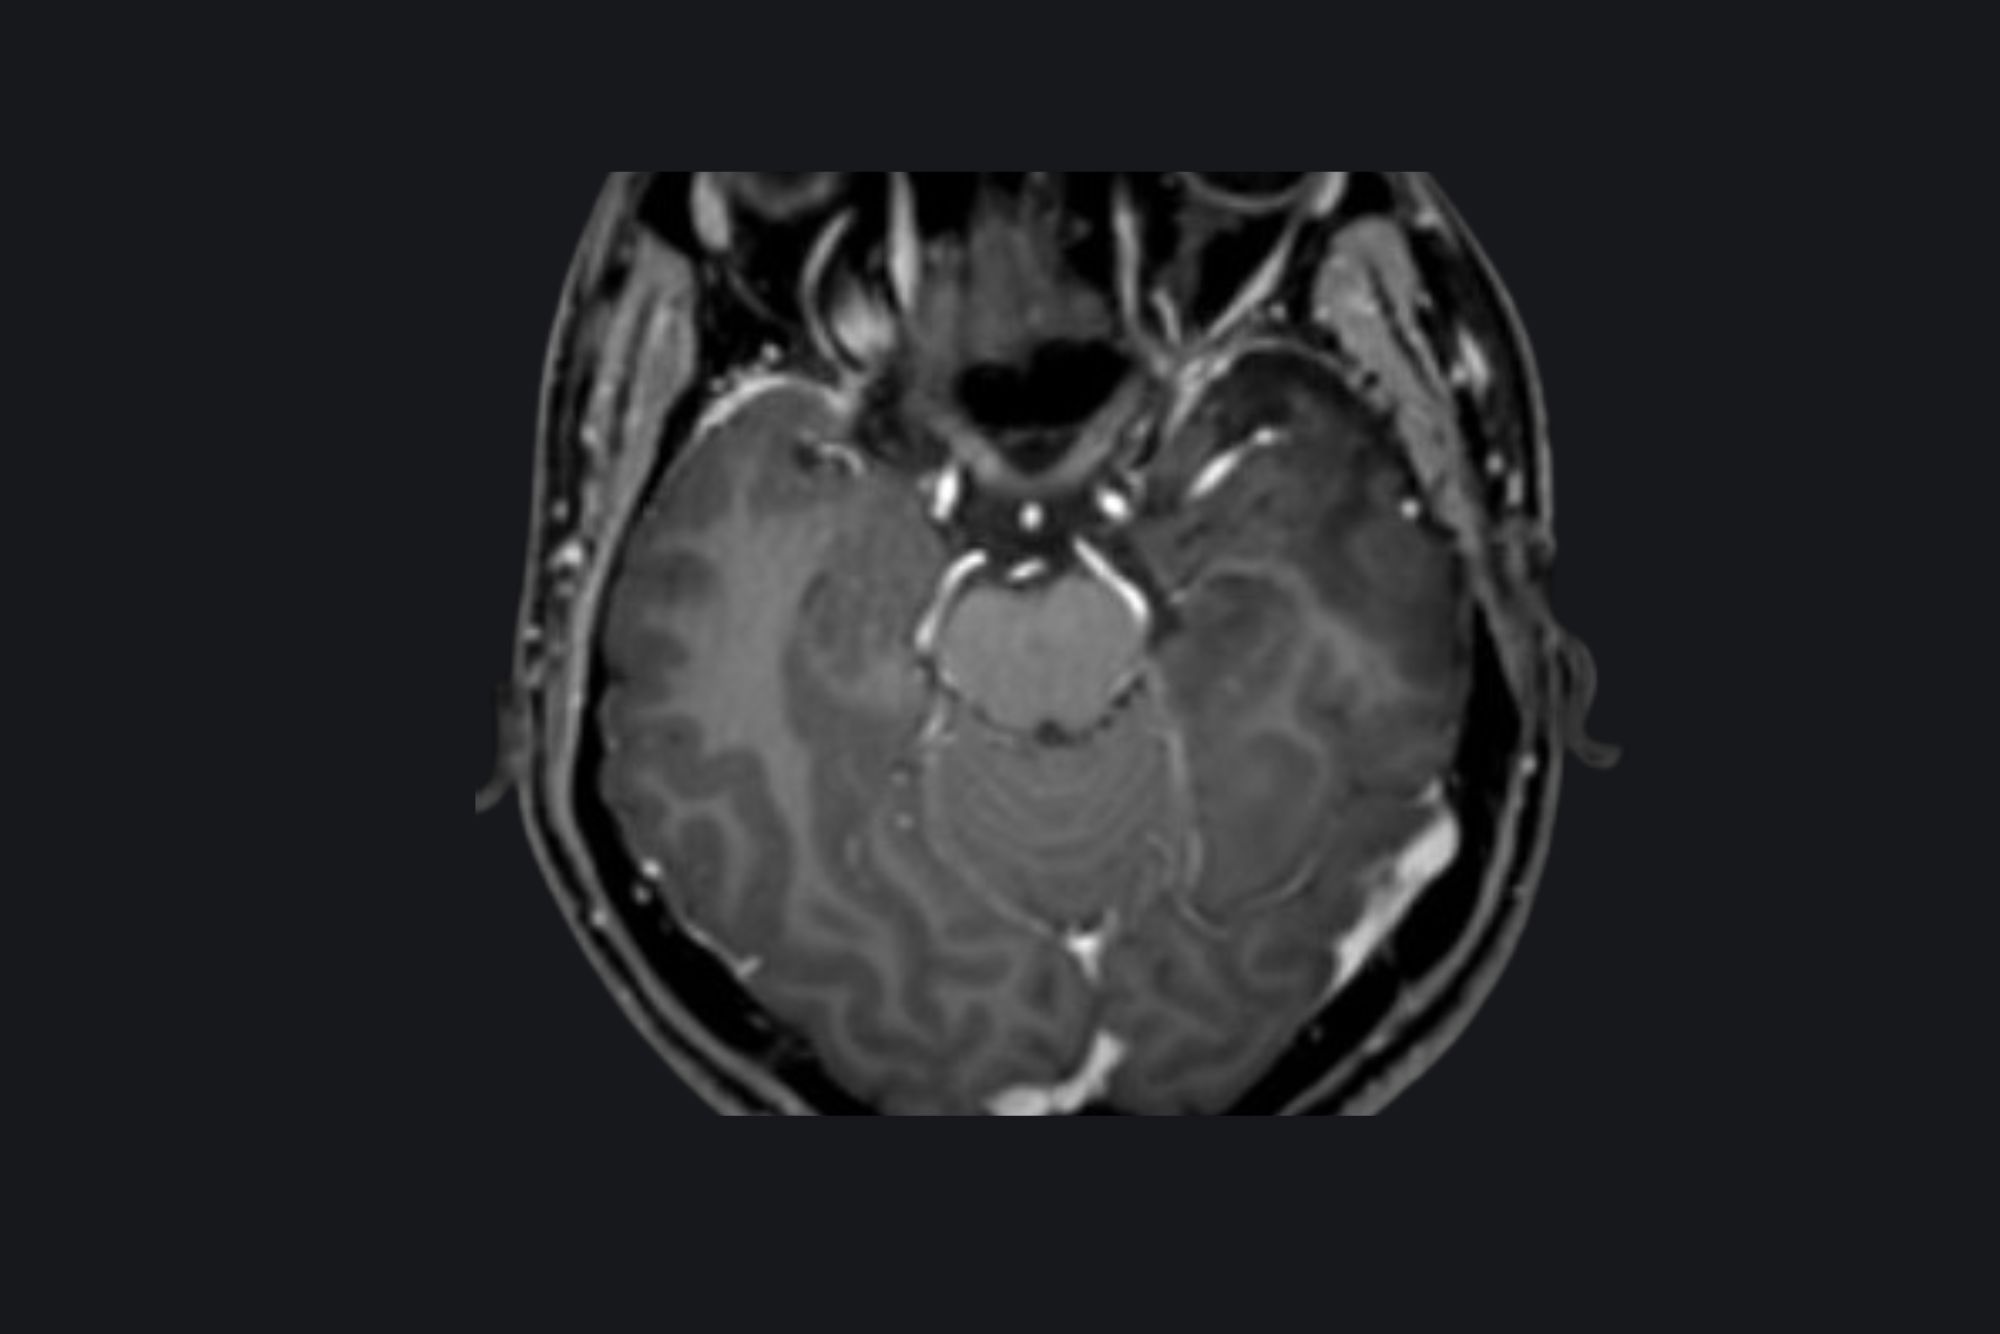

Cavernoma

Preoperative MRI